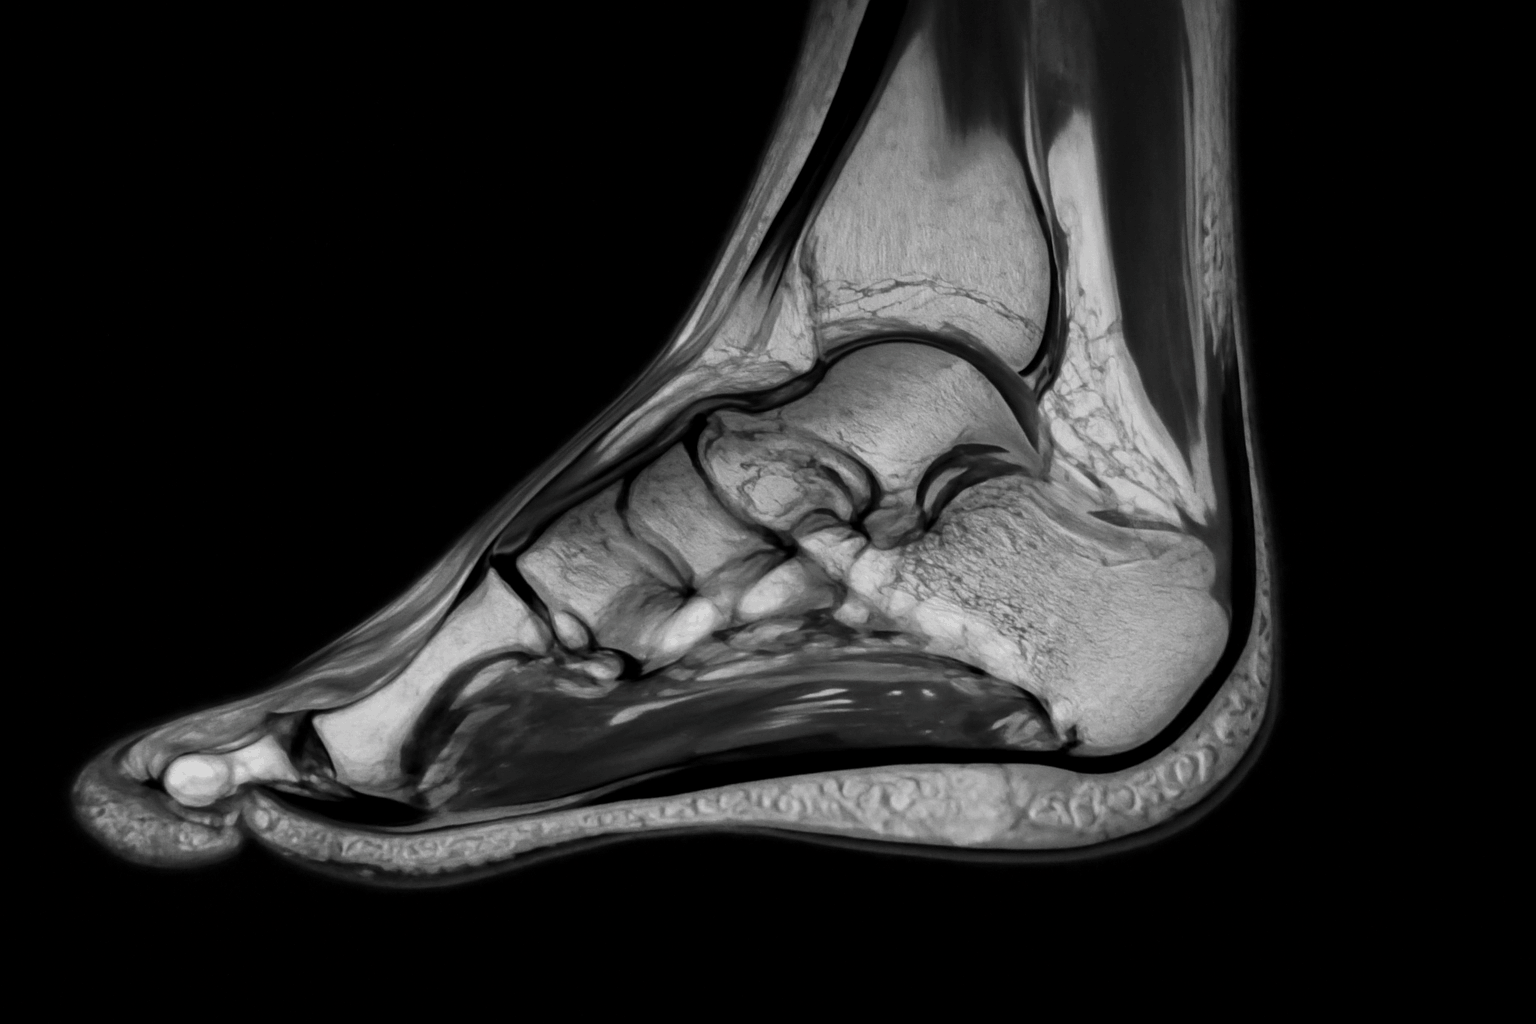

МРТ стопы в Долгопрудном представляет собой современный и высокоинформативный метод диагностики. Этот инструмент позволяет получить детальные изображения мягких тканей, суставов и костей стопы, что существенно помогает в установлении точных диагнозов. Процедура выполняется с использованием магнитного поля и радиоволн, не требуя применения ионизирующего излучения.

Состояние стопы зачастую влияет на общую мобильность человека, поэтому раннее выявление возможных заболеваний становится первостепенной задачей. Уникальность метода заключается в его способности отображать изменения на ранних стадиях, что значительно увеличивает эффективность лечения.

Что может выявить МРТ?

Процедура предоставляет возможность обнаружить широкий спектр заболеваний и состояний. Рассмотрим основные патологии, которые может выявить это обследование:

- Переломы и трещины.

- Воспалительные заболевания: артриты и тендиниты.

- Травмы мягких тканей: повреждения связок и сухожилий.

- Опухоли.

- Дегенеративные изменения: артрозы.

- Кисты и абсцессы.

Эти результаты помогают врачам установить точный диагноз и определить дальнейшее лечение, что значительно повышает эффективность медицинской помощи.